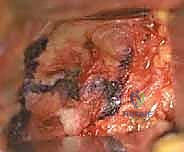

هذا الاصطدام المتكرر يشبه "المطرقة والسندان". بمرور الوقت، يؤدي هذا الاحتكاك العنيف إلى سحق أو تمزيق الشفا الحقي (Labral Tear)، وتقشير أو كشط الغضروف المفصلي الناعم من على عظم الحوض. عندما يتلف الغضروف، ينكشف العظم الأساسي، وتبدأ رحلة الألم المزمن وخشونة المفصل (Osteoarthritis).